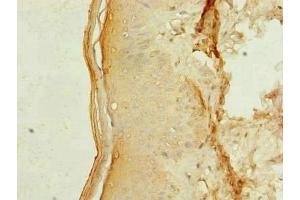

L’anticorps anti-MEI1 Polyclonal Lapin est utilisé pour la détection de MEI1 dans des échantillons de Humain. Il a été validé pour ELISA et IHC.

ELISA, Immunohistochemistry (IHC)

AA 1-238

Recombinant Human Meiosis inhibitor protein 1 protein (1-238AA)